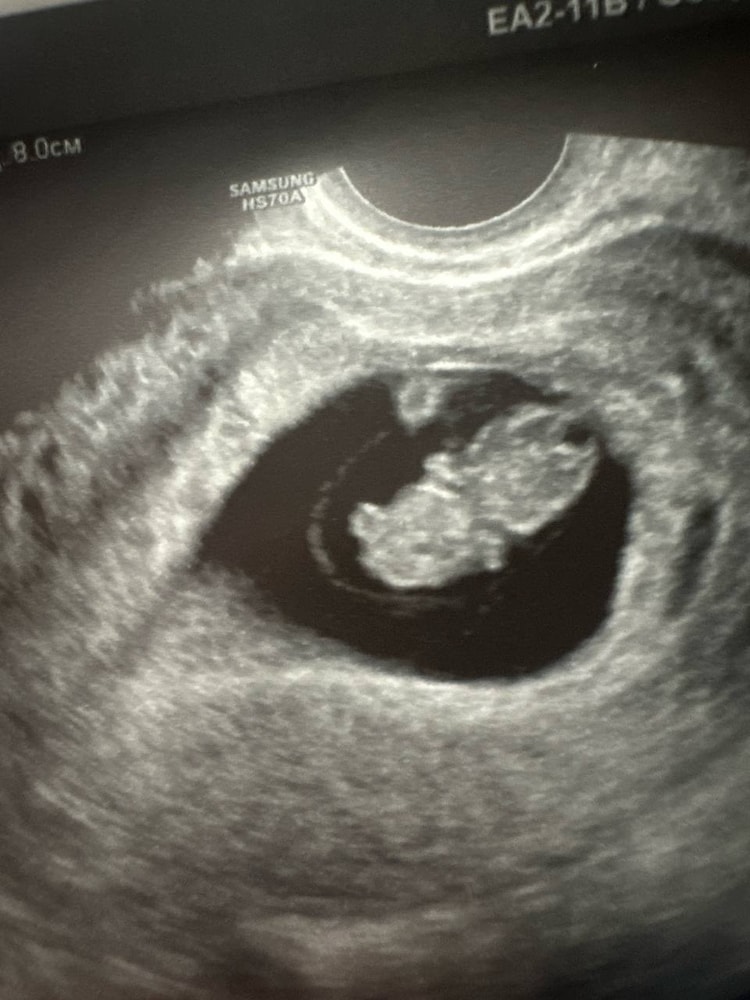

наши 8 недель и 3 дня вместе

Наши будни, наши неделькиКТР - 20,4мм

ЖМ - 4,9 мм

чсс 174 уд/мин

вчера уже зафиксировали шевеления пироженки)

С 4 недель со мной гематома, стала чуть меньше, но все же не прошла полностью. Регулярные коричневые выделения, опорожняется по-тихонечку. Я на дюфастоне 3 раза в день.